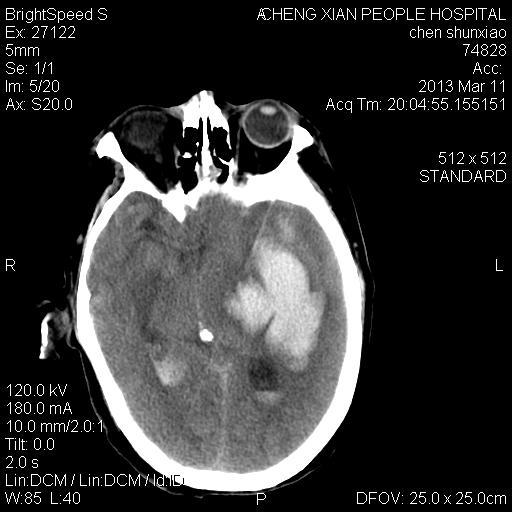

患者陈++,男,71岁。因“昏迷四小时,伴右侧肢体活动受限”以“脑出血”收住院。发病后12小时用“改良立体定向-软通道微创介入新技术治疗脑出血”。术后24小时颅内出血大部被清除,患者神志清晰。右侧肢体肌力0级。

患者陈++,男,71岁。因“昏迷四小时,伴右侧肢体活动受限”以“脑出血”收住院。发病后12小时用“改良立体定向-软通道微创介入新技术治疗脑出血”。术后24小时颅内出血大部被清除,患者神志清晰。右侧肢体肌力0级。